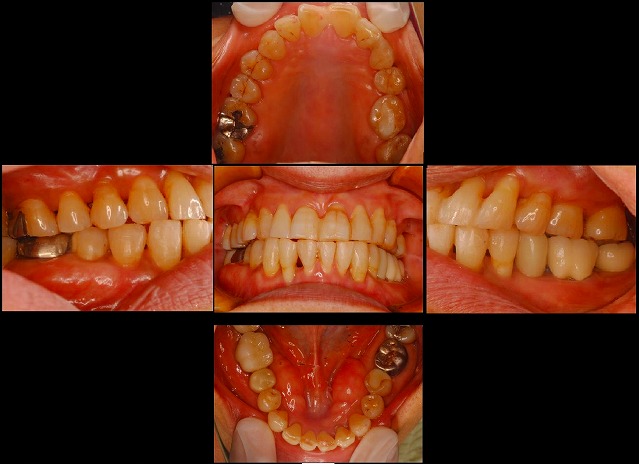

そして、治療終了後の写真です。

上顎は今回は矯正せず、下だけでの矯正ですが、下がきれいになると自然にある程度そろって綺麗になっています。

左下の奥の歯が無くてミニインプラントをした所には、普通サイズインプラントを後から入れましたので、歯が一本増えています。

全体で二年間の治療でした。お疲れ様でいした。